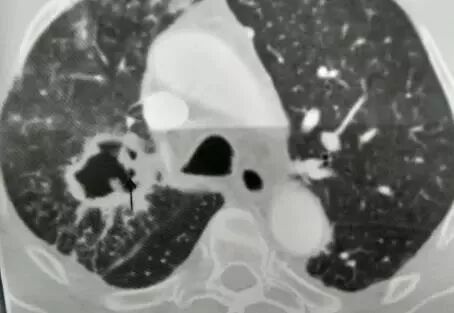

这是什么?

答曰:几乎是鳞癌。

为什么?

因为:鳞癌最容易烂掉!鳞癌天生的烂!乱七八糟的空洞,肿瘤内液化坏死,等等,大部分是鳞癌

肿块+液化坏死 ≈ 鳞癌。